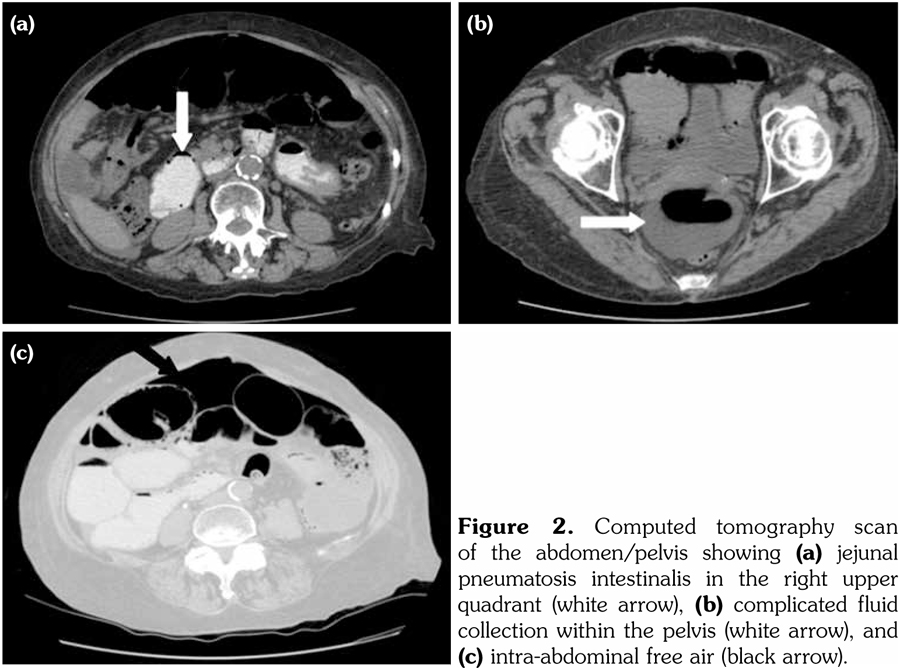

An abdominal computed tomography (CT) scan revealed large volume intra-abdominal free air, moderate intra-abdominal free fluid with no extravasated contrast, pneumatosis of the proximal jejunum with dilatation up to 5.8 cm, and a transition point (Figure 2). These findings raised concern for acute bowel ischemia, volvulus, and possible perforation.